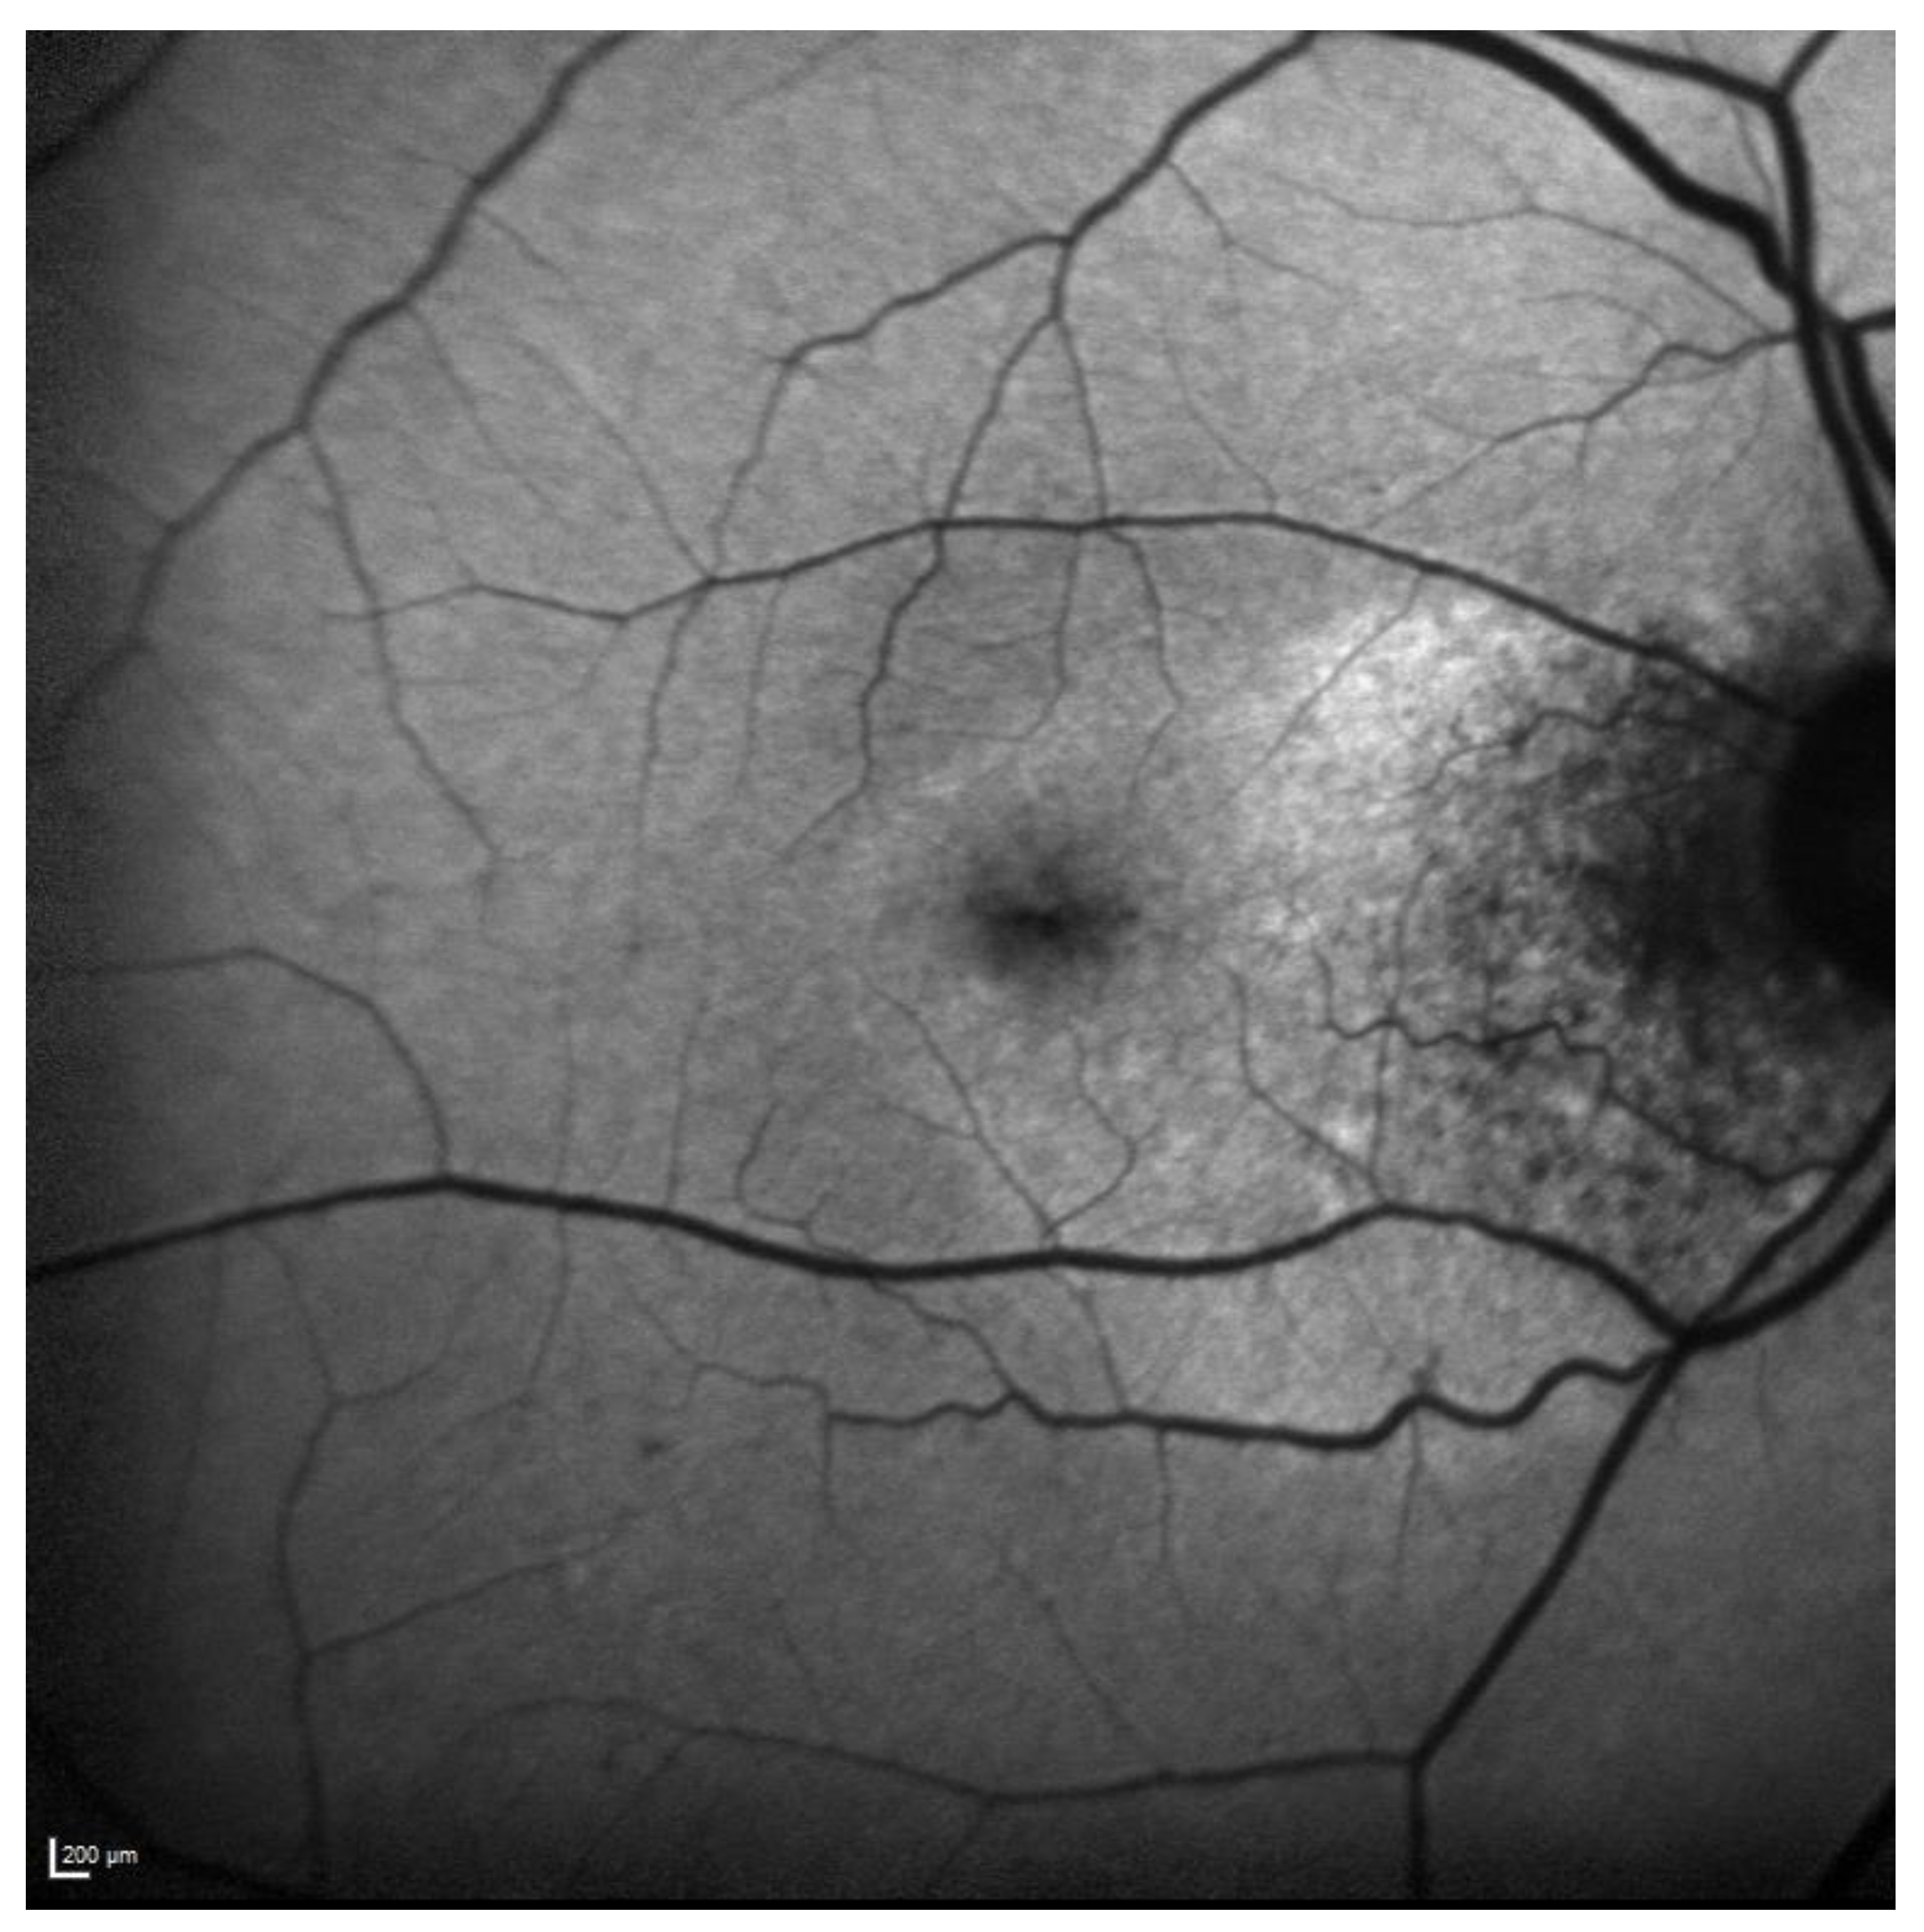

FAF revealed a hypoautofluorescent macular lesion in the left eye (Figure 8).

Figure 8.

Case 6. Heidelberg Spectralis blue autofluorescence shows a left eye macular hypoautofluorescent lesion.